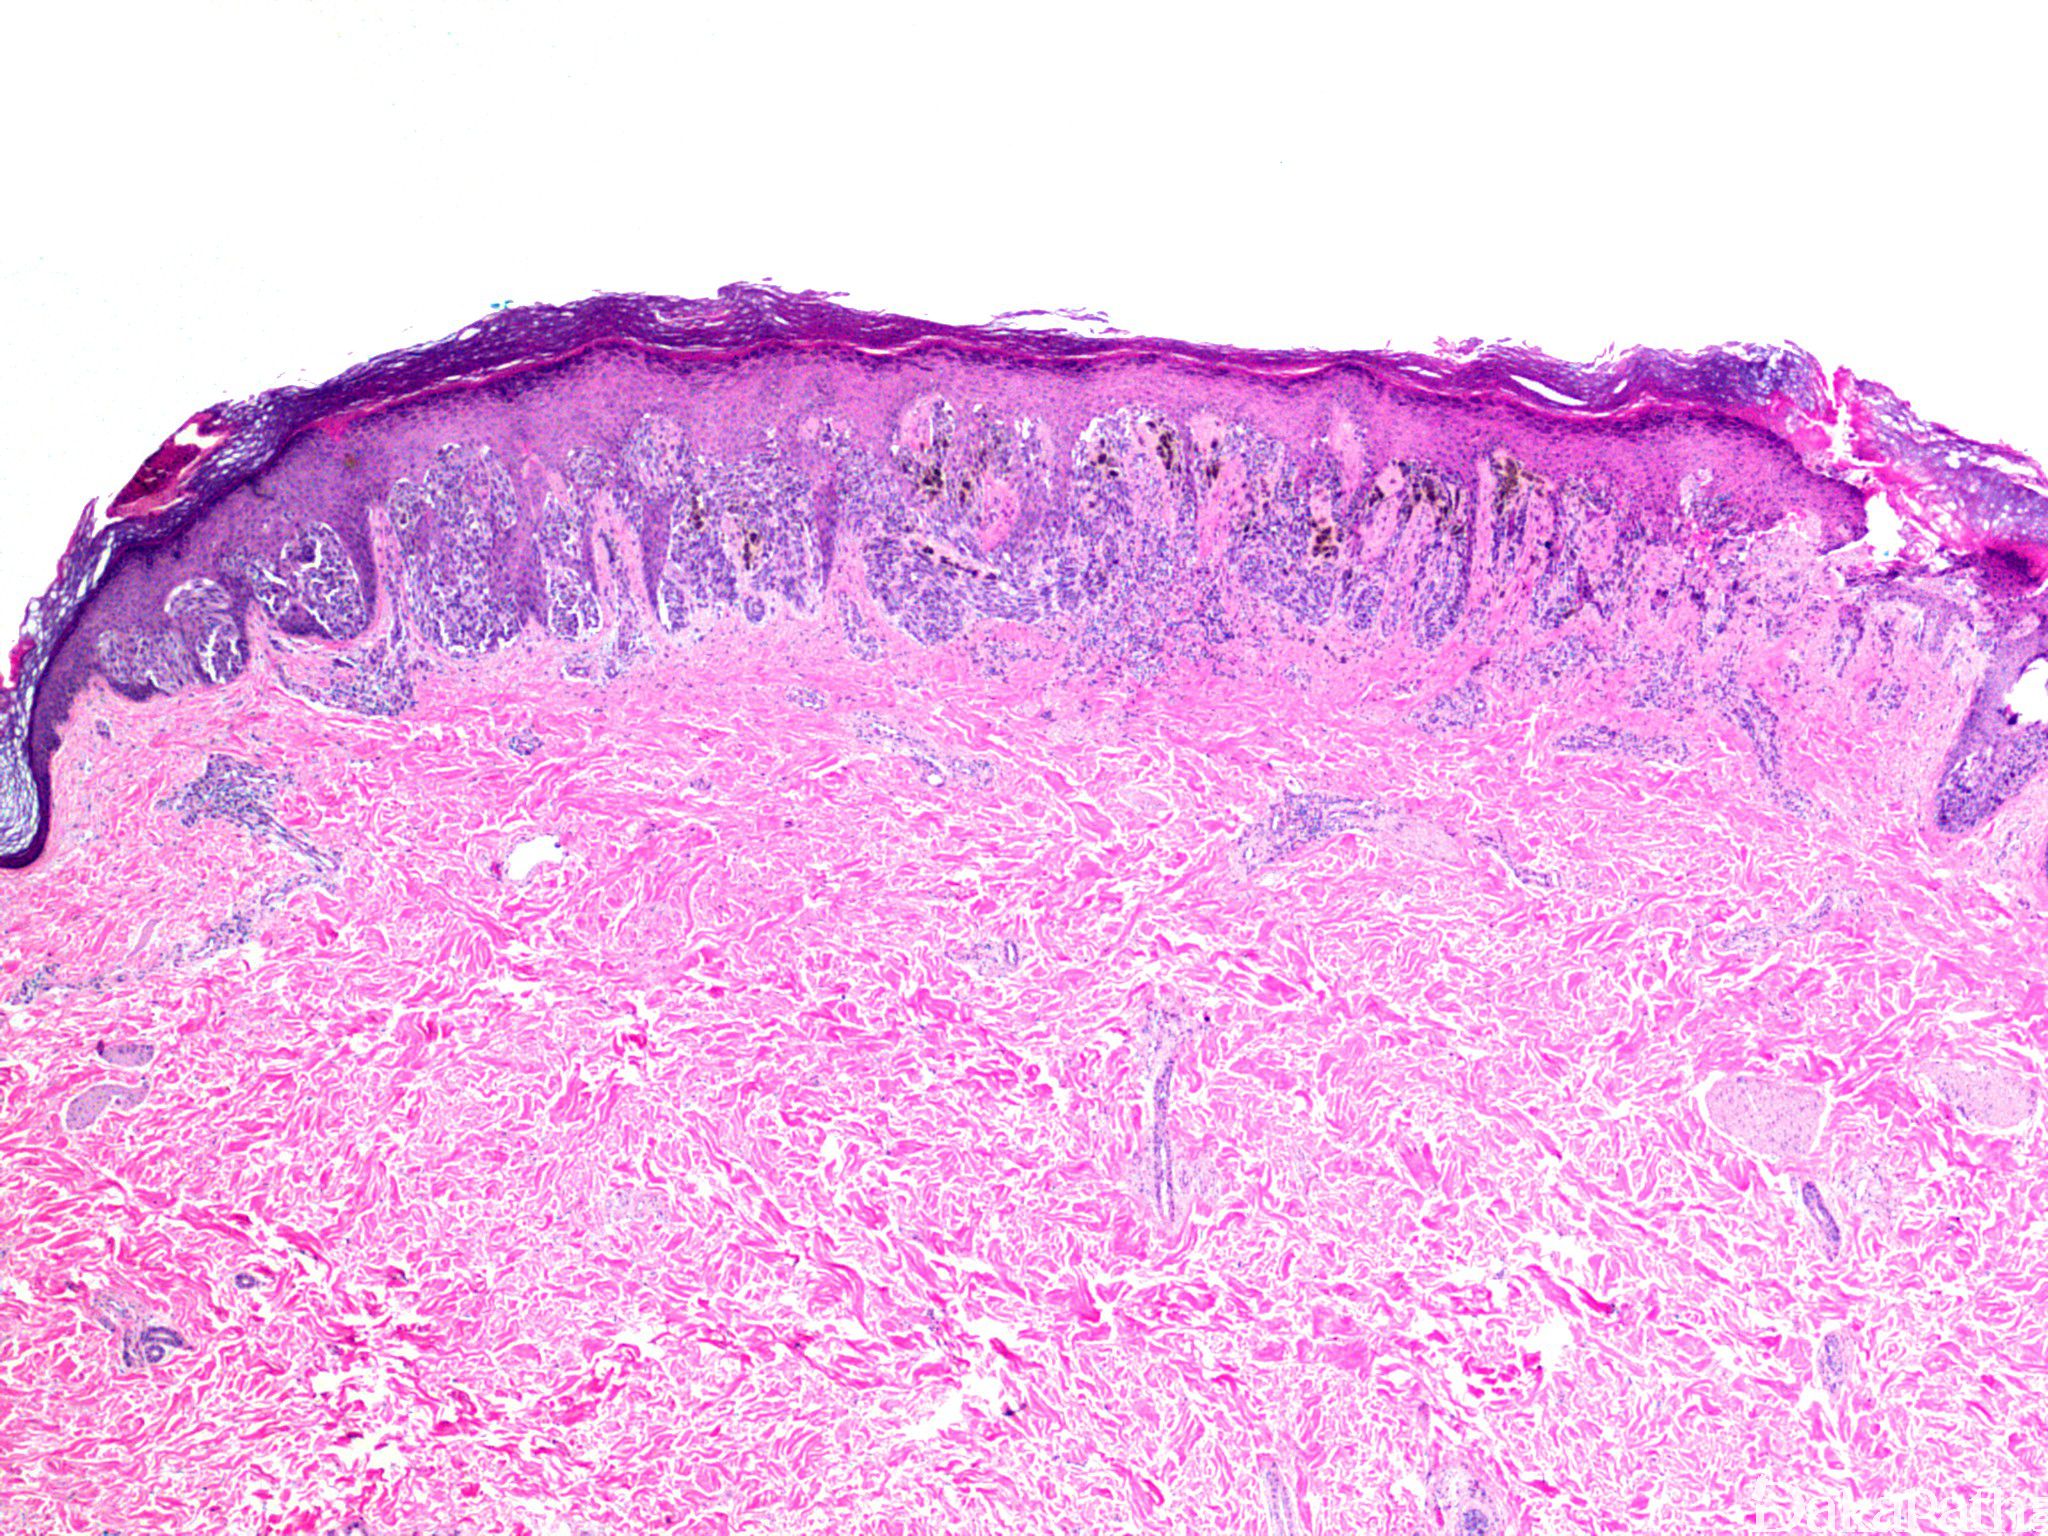

病变边缘界限清楚,对称性生长,具有成熟现象,复合性和真皮内 Spitz 痣常呈楔形;

间质血管丰富、扩张,水肿,可见散在的淋巴细胞聚集;

交界性或复合性 Spitz 痣部分病例梭形细胞呈紧密束状排列,与上皮脚平行,如悬挂的香蕉一样;交界处黑色素细胞巢常见“裂隙”;可见核分裂,但通常很少见并且局限在细胞密集病变的表浅部位;

病变常小而对称,界限清楚;